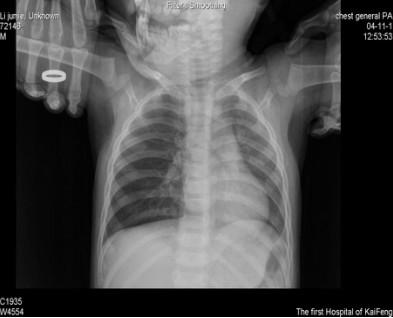

男性幼儿,1岁咳嗽哮喘月余,摄片吸气相胸片一切正常(如下图所示),如果没有经验很容易漏诊。我们知道,小儿气道异物病多见于3岁以下幼儿,对此类患儿使用动态DR检查为首选。

结合动态DR透视观察到肺野透亮度、纵膈摆动及位置运动变化,加拍高清(900万像素)的呼气相胸片后,最终确诊为右支气管呼气性活瓣性阻塞。